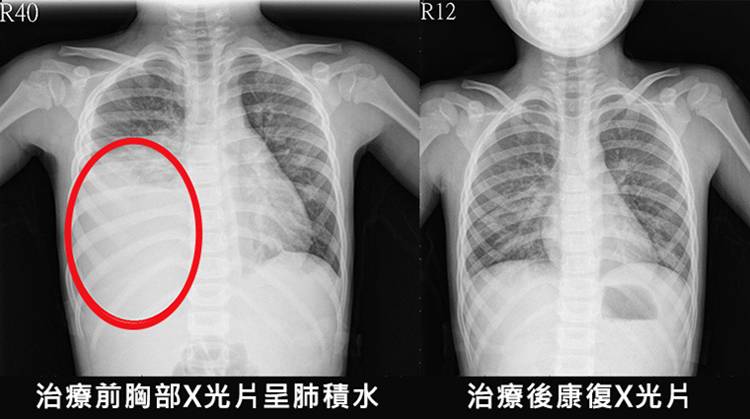

劉小姐是一名教師今年55歲 十分重視養生 平時都有參加晨跑活動,但最近半年裡,我在校內上下樓梯時,發現會有點喘不過氣,晚上睡覺時也開始會咳嗽,直到上個月咳到不像話「快咳出血來」甚至得坐著睡覺才能入眠,就醫檢查才發現是「肺積水」惹的禍,但是吃了很多藥也沒有任何的改善,反而越來越嚴重,夜夜難以入眠...一活動就喘不過氣,不願意下床,無法外出,有時還依賴呼吸器。為治這病花了不少錢,女兒回家時候帶回來了這個咳喘珍稀藥(橘紅顆粒)說是興許能徹底治好我的「肺積水」。我每天堅持服藥,沒想到這個藥效如此強,三四天就感覺呼吸均勻多了,用了一個週期病情就得到極大好轉,夜裡也能入睡了。兩個週期後肺積水徹底好了,不會一活動就喘不過氣來,現在的我呼吸也越來越順暢,胸痛,浮腫、心率加快,心律不齊的症狀明顯改善。睡眠質量提高了,人精神了很多。